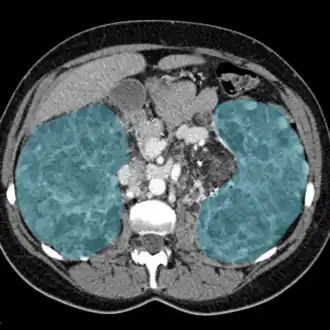

| Rins inflamados em exame de ressonância magnética (em azul). | |

Nefrite (do grego - nephrós - rim + itis - inflamação, pelo latim nephrite), também chamada nefroflegmasia (forma em desuso), consiste na inflamação dos rins, responsável por metade dos problemas renais.[1]